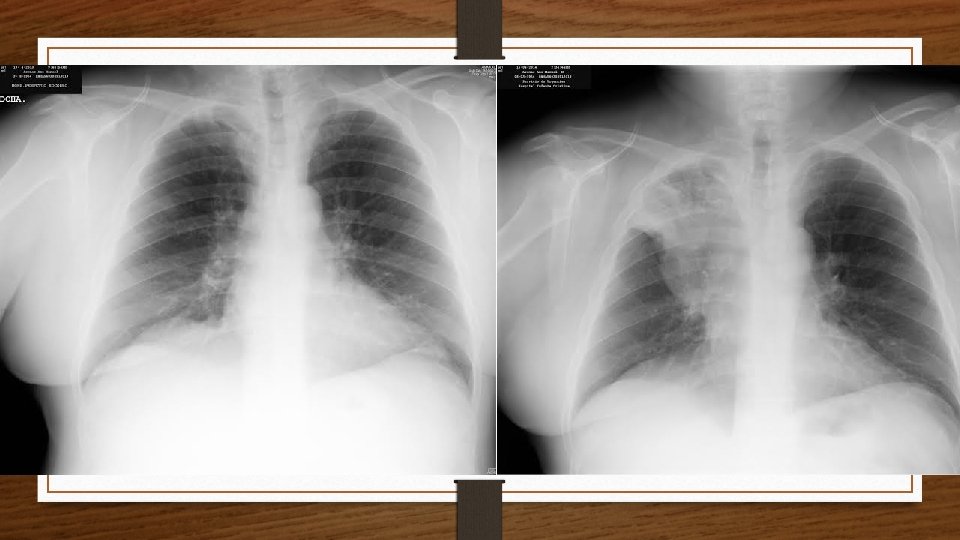

Radiografía de Tórax

RESUMEN • Paciente varón de 60 años fumador • Dolor torácico derecho + disnea + hemoptisis + edema facial/cervical + cambio en el tono de voz • Exploración: edema facial/cervical, hipoventilación CSD + IY • Rx: Masa en LSD (Signo de Golden) • TC Tórax: masa pulmonar LSD que se extiende a mediastino con una cava superior filiforme.